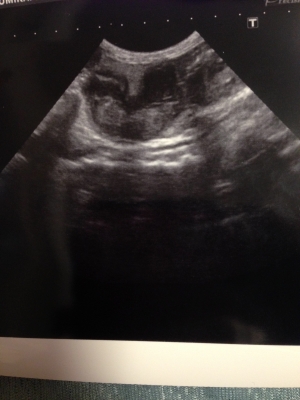

JUGEMテーマ:ハリネズミ 通院3日目。 院長先生の診察。 エコー検査をしてもらった。 子宮と卵巣がかなり肥大して、中に何かが溜まっているとのこと。 悪玉菌が落ち着いてきているし、体力があるうちに手術したほうが良い。 できれば今日やりましょう!!!と説得を受けた。 素人の私が見ても子宮が悪いのがわかるし、院長の言葉を信じて、手術をお願いした。 3時間くらいかかるので、一旦帰宅。 緊張で喉がカラカラ。 とりあえず、chulaのケージを掃除して時間を潰した。 病院から電話があり、無事に手術が...